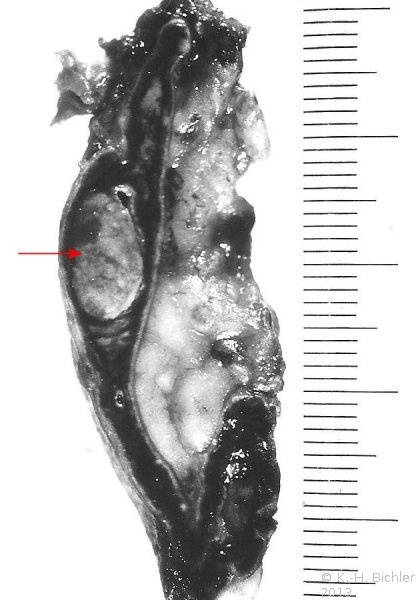

Die zur Blutprobengewinnung durchgeführte beiderseitige Etagenvenographie zeigte rechts einen 1-2-cm großen und links einen 4-5-cm großen Tumor (Abbildung 3).

Therapie: Operativ bestätigte sich der beiderseitige Befund (Abbildung 4, s. Abbildung 1a).

Histologisch bestanden beide Tumoren aus Wucherungen von polymorphen, in Balken und Strängen angeordneten Nebennierenmarkzellen mit wechselnd großen Kernen (s. Abbildung 1b).